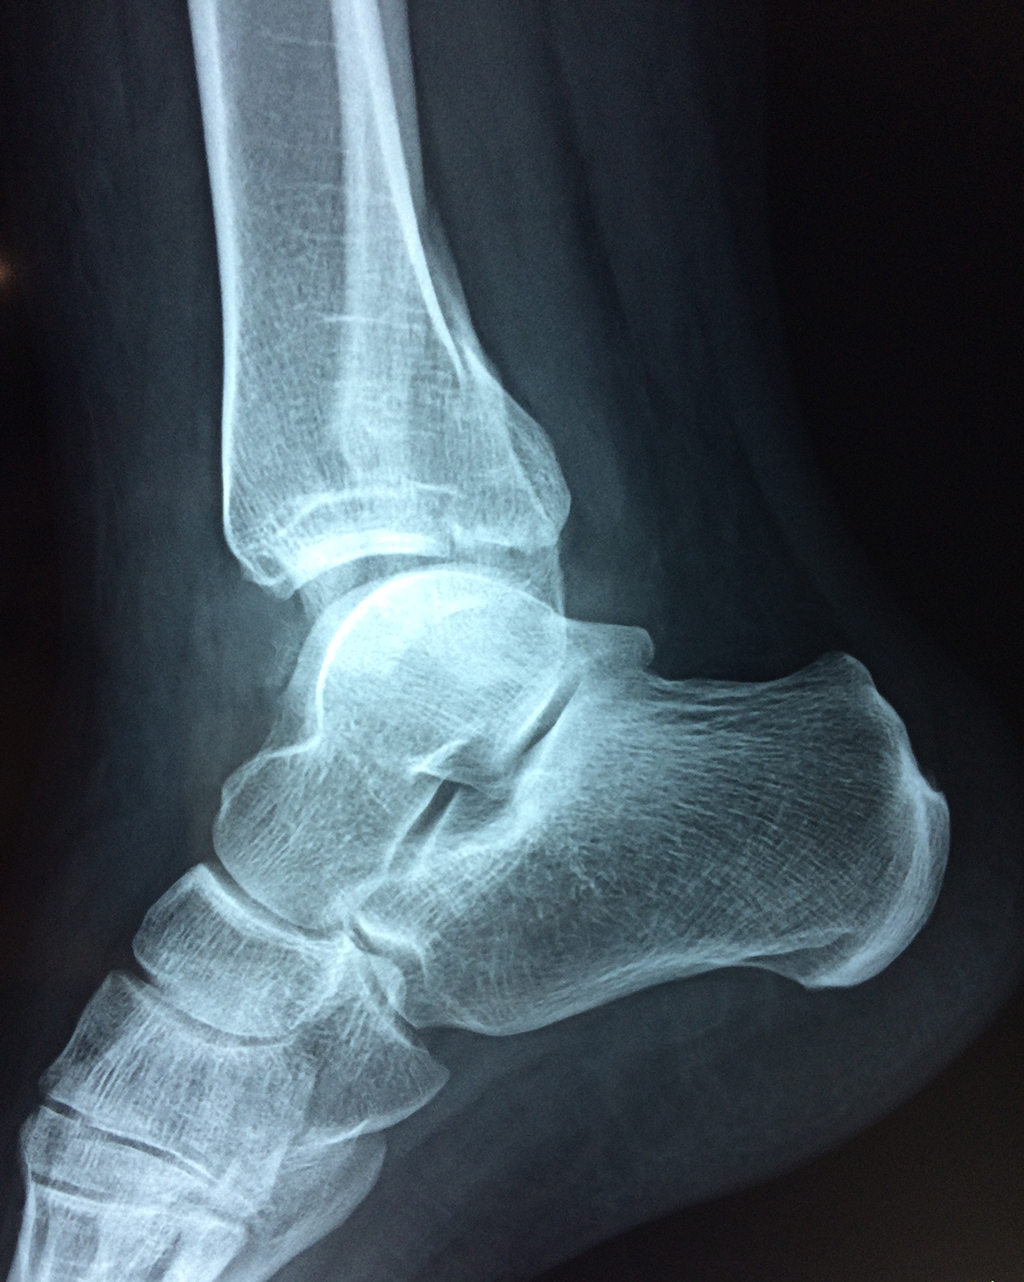

Una fractura de tobillo es la rotura de uno o más de los huesos del tobillo. Estas fracturas pueden ser:

- La fractura se extiende hasta la articulación del tobillo (fractura intra-articular).

- Los tendones o ligamentos (tejidos que sujetan los músculos y los huesos entre sí) están rotos.